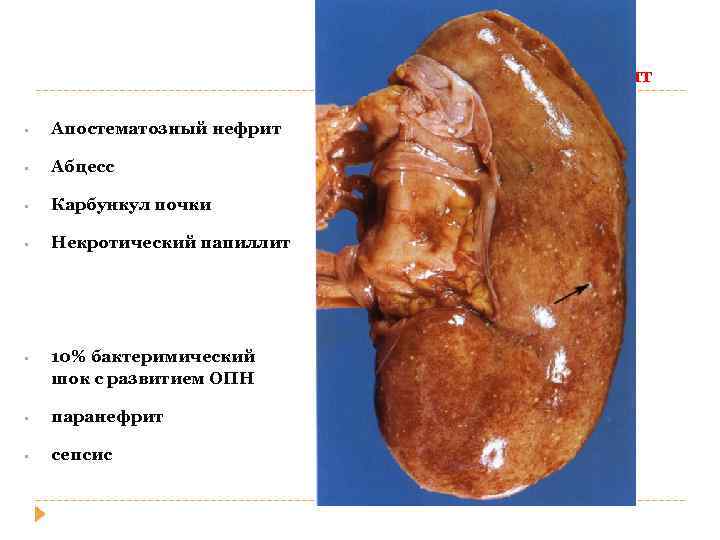

Острый пиелонефрит • Апостематозный нефрит • Абцесс • Карбункул почки • Некротический папиллит • 10% бактеримический шок с развитием ОПН • паранефрит • сепсис